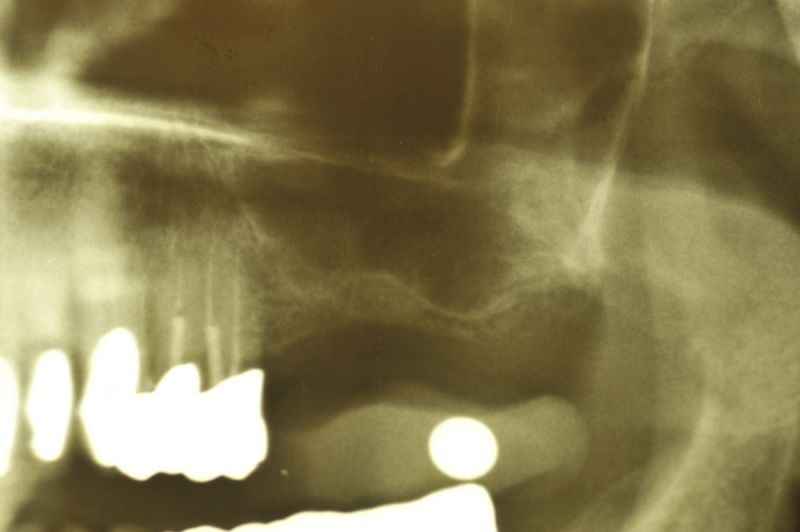

76 jährige Patientin mit 2 Implantaten und externem Sinuslift

Am heutigen Tag sind in regio 26 und 27 zwei Implantate mit einem externen Sinuslift versorgt worden. Die Besonderheit des Eingriffs liegt darin, dass im Oberkieferseitenzahnbereich, bei einer noch vorhandenen Restknochenhöhe von wenigen Millimetern, zwei Implantate gesetzt und gleichzeitig eine Aufdoppelung des vorhandenen Restknochenangebots, durch die Schaffung eines Raumes zwischen knöcherner Abgrenzung der Kieferhöhle und der in die Kieferhöhle hinein verdrängten Kieferhöhlenmembran geschaffen werden konnte.

Genau das kann man dann auf dem Röntgenbild erkennen. So bildet sich innerhalb der Kieferhöhle, aber begrenzt durch die Kieferhöhlenmembran, neuer Knochen, der dann nachfolgend dem Implantat den knöchernen Halt gibt, den es unter späterer Belastung durch Kaudruck benötigt.